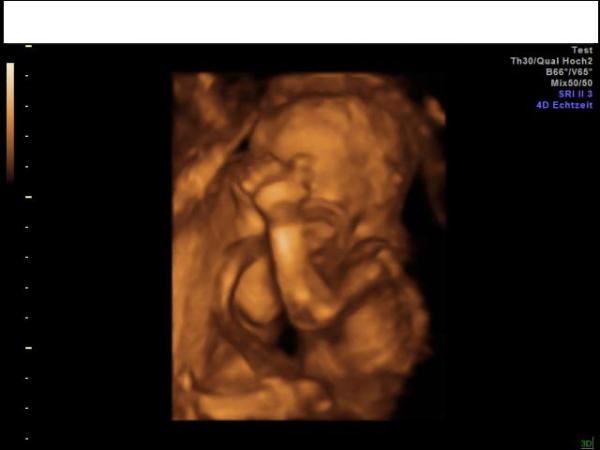

Hallihallo, nach 4 langen Wochen war heute wieder VU angesagt. Es ist alles bestens, das kleine wiegt 336 g. Schöne 4D-Bildchen gab es auch wieder, ich hänge euch eins an. Die Hebamme hat mir auch den ersten Termin für den GVK gesagt, am 5.1. gehts los. Ein Outing hatten wir heute auch Der Verdacht der 17. SSW hat sich bestätigt. Verraten kann ich es hier leider nicht, wollen es bis zur Geburt geheim halten, weiß ja nicht wer hier noch so alles mit liest Nun darf ich in 3 Wochen wieder hin, da meine FÄ dann Urlaub hat. Glückliche Grüße.

Bild zu Heute VU gehabt - Forum für März - Mamis